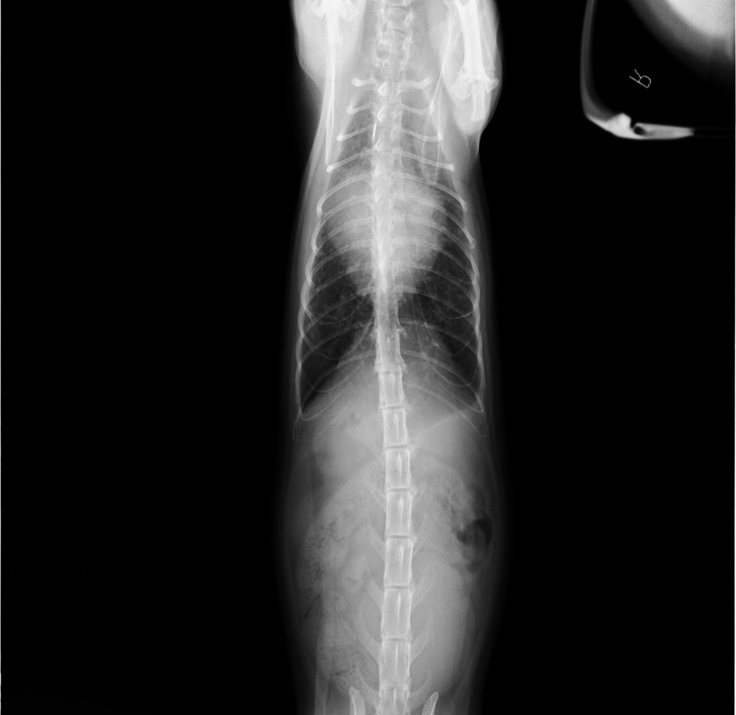

2019年5月頃

軽い咳が続き、心配になったので病院に連れていきました。

その時のレントゲン写真です。

この時は、肺が少し白いことから、気管支炎と診断され、

薬をもらい様子を見ることにしました。